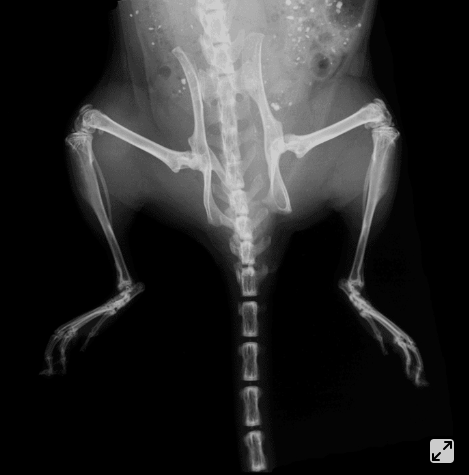

瑞孚迪(Revvity)全新一代小动物活体成像系统IVIS Lumina X5整合了最佳的高通量生物发光、荧光及高分辨率二维X光成像模块。扩展为五只小鼠的光学及X光大成像视野、独特的实验设置和样品标记辅助配件让研究人员能更便捷、更快速地获取疾病进展中解剖学和功能学各方面的稳定数据和答案。详言之,高分辨率X光图像与高质量光学图像数据的整合能力使其成为业界最顶 级的二维多模式活体成像系统。另外,IVIS Lumina X5包含先进的光谱分离功能,可通过高灵敏度多光谱成像来监测同一动物体内的多个生物学事件。

高通量光学及X光成像(同时成像5只小鼠)

支持小鼠及大鼠成像